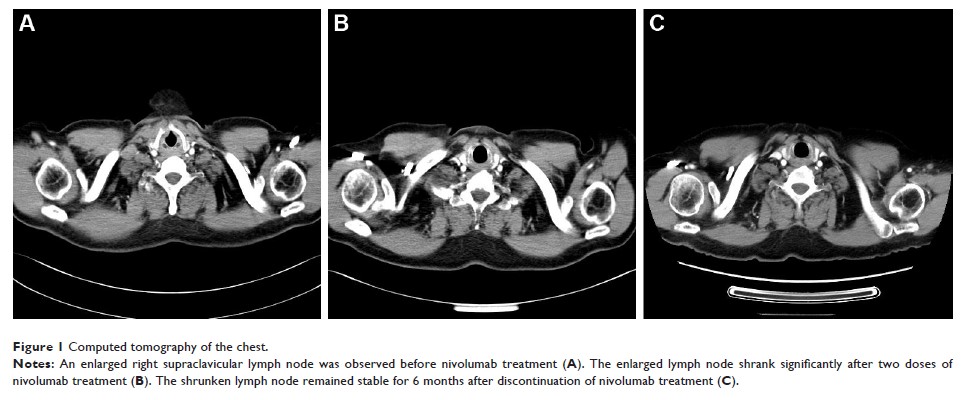

Case Report

- 作者:Yan Zhu, Hong Hua Wu, Wei Wang

- 期刊:OncoTargets and Therapy